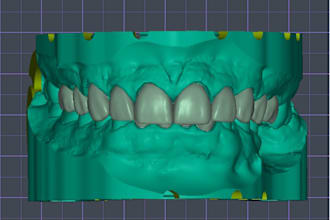

I will do dental prosthesis crown design using exocad, 3shape, inlab and cerec

From $20